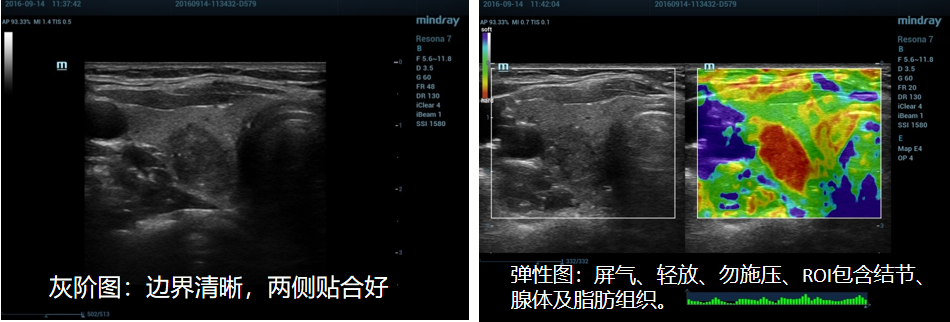

4、正确示范:

(1)乳腺应变式弹性成像(脂肪层出现蓝色带):

(1)甲状腺应变式弹性成像(脂肪层出现蓝色带):